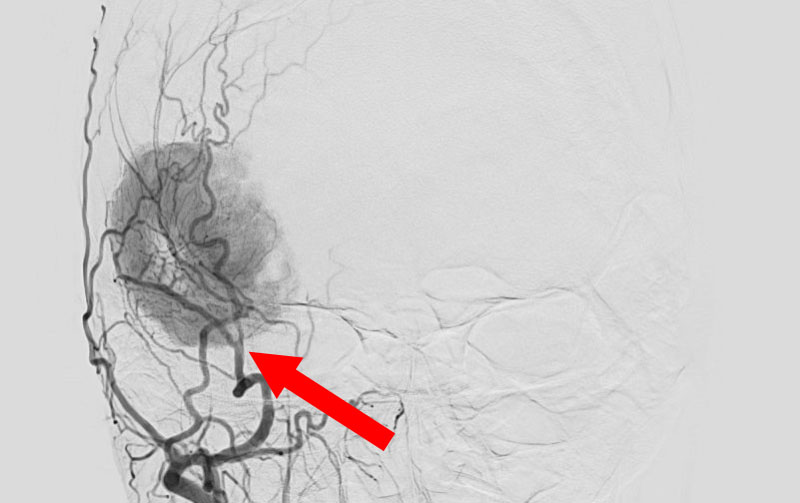

1598

'25年11月26日

右円蓋部髄膜腫

40代

大阪府の病院

治療

後